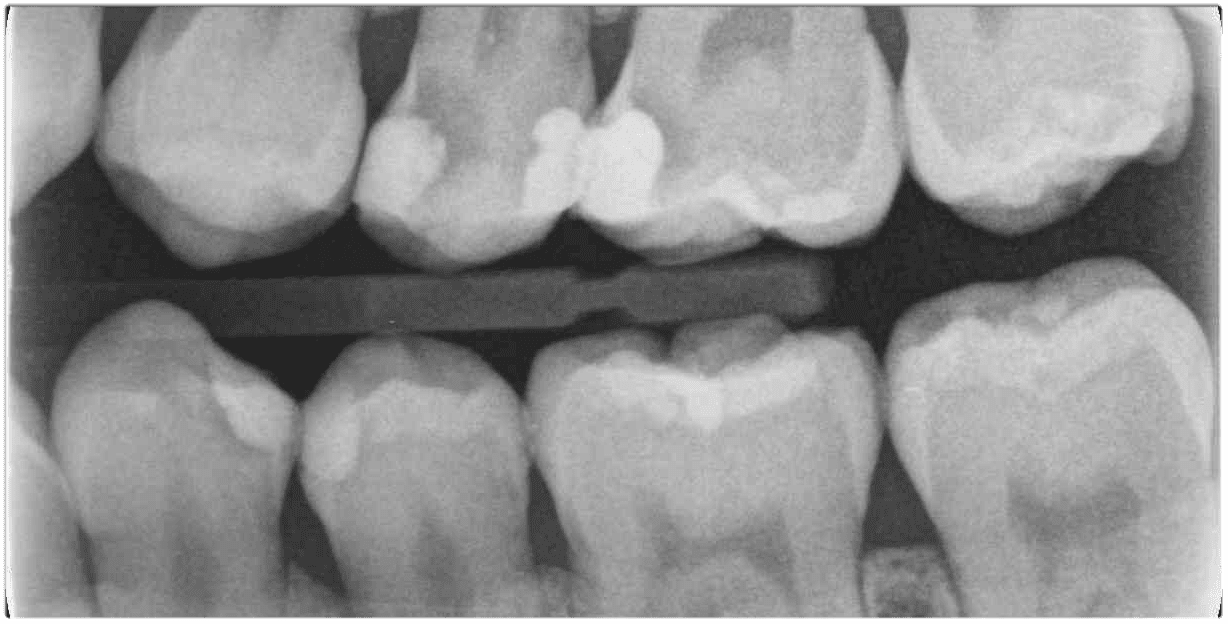

當今國人最嚴重的口腔疾病之一就是蛀牙,當蛀牙範圍嚴重到接近牙齒的神經或是已經有輕微的發炎症狀,往往牙醫師會跟你說要抽神經才能根深蒂固的清潔病菌,解決你的牙痛問題 …